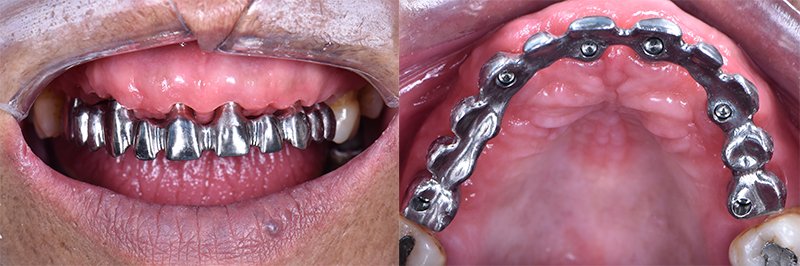

Após o planejamento integrado cirúrgico-protético do caso, foram realizadas exodontias dos elementos 13 a 23, 15, 24 e 25, sendo imediatamente instalados seis implantes Implacil Due Cone com 11 mm de comprimento e 3.5 mm de diâmetro (Implacil De Bortoli), com precisão no posicionamento tridimensional do implante. Visando o condicionamento gengival e a formação de um perfil de emergência adequado, após a instalação de mini pilares Implacil com cinta de 4.5 mm, foi instalada uma prótese fixa provisória imediata (Figura 4). Após dois meses, uma radiografia panorâmica foi realizada para verificar a osseointegração dos implantes (Figura 5), visando o início da reabilitação protética definitiva.

Para a reabilitação protética definitiva, após a remoção da prótese provisória (Figura 6), foi realizado o escaneamento do rebordo maxilar e da posição dos implantes utilizando o scanner 3Shape (3Shape). Após o posicionamento dos scan bodies da 3Shape, foi realizado o escaneamento do rebordo. Em seguida, procedeu-se o escaneamento do arco maxilar com a prótese provisória em posição e do arco antagonista com a prótese parcial removível da paciente em posição (Figura 7).